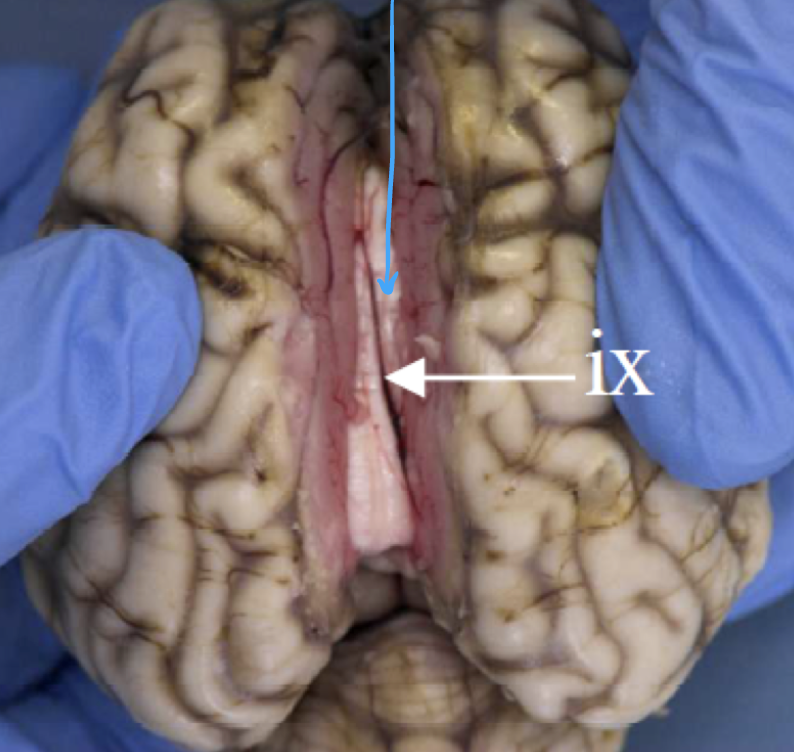

what structures are shown here

internal capsule

corona radiata